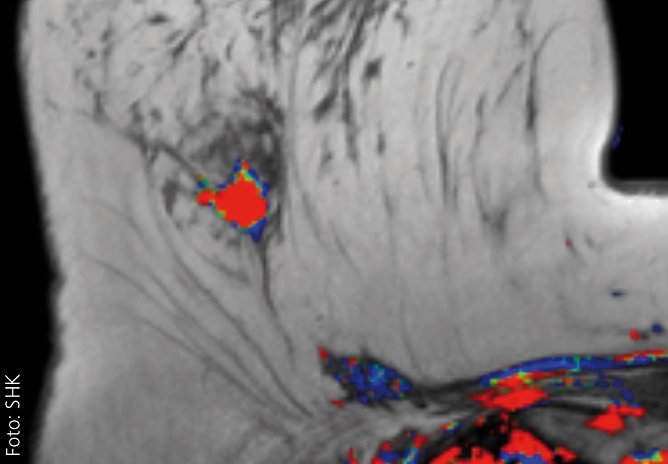

Bildgebung bei Mammakarzinom im Fokus

In den vergangenen Jahren hat sich die Palette möglicher Bildgebungen von Tumoren der Brustdrüse deutlich weiterentwickelt. Dies ist insbesondere technischen Innovationen in der Radiologie zu verdanken. Eine frühe Tumordiagnostik ermöglicht bessere therapeutische Optionen und erhöht häufig die Aussicht auf Heilung...

Der Vortrag stellt die aktuellen Möglichkeiten der Bildgebung der Brustdrüse vor und erläutert die innovativen technischen Weiterentwicklungen der jüngsten Zeit sowie die hier verfügbaren Optionen der histologischen Sicherung. Hinzu kommt ein kurzer Einblick in die sogenannte bildgebende Nachsorge, also die radiologische Diagnostik nach behandeltem Mammakarzinom, die wichtig ist, um ein neuerliches Tumorleiden auszuschließen. Es wird auch auf häufig geäußerte Ängste betroffener Frauen eingegangen werden und wie gewohnt Gelegenheit zum gemeinsamen Gespräch geben.